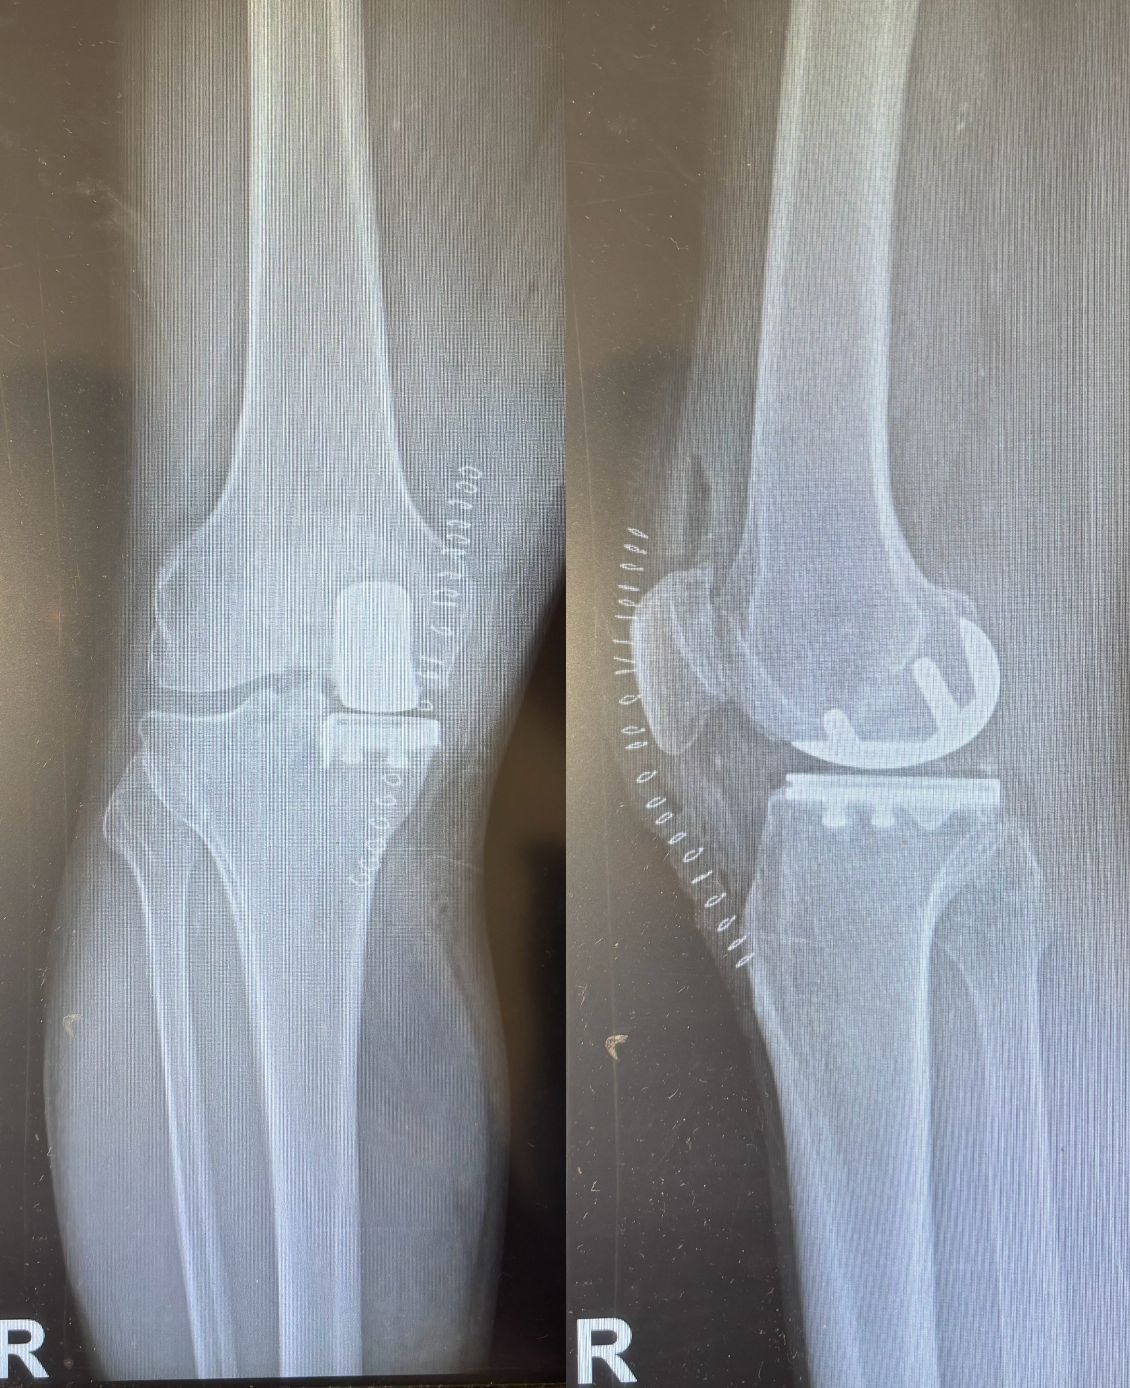

Ho maturato una solida esperienza nella chirurgia protesica mini-invasiva di anca e ginocchio. Eseguo interventi di protesi di anca mediante accesso anteriore “bikini” e accesso posterolaterale, interventi di protesi di ginocchio sia monocompartimentale che totale. Tratto la traumatologia sportiva di ginocchio e spalla mediante l’utilizzo di tecniche artroscopiche mini-invasive.